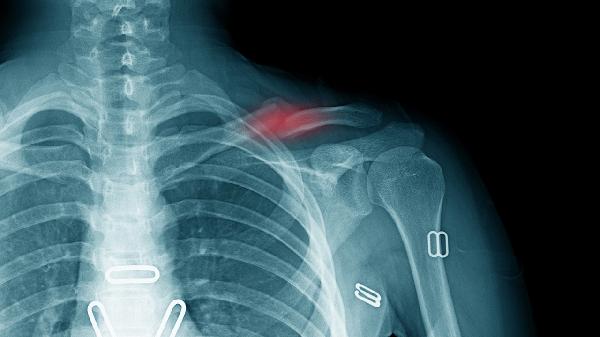

二、X射线的小脾气

1.辐射量的小算盘

整套检查的辐射量约等于连续拍几百张胸片的数值,但现代设备会像智能空调般自动调节射线强度。医护人员还会给甲状腺等部位戴上特制"围裙",把辐射量压缩到安全范围。